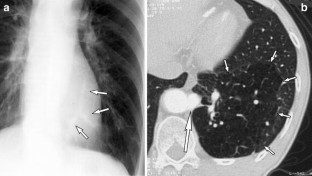

Fig. 2